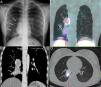

Observación clínicaCaso 1 (fig. 1)Mujer de 16años con neumonías de repetición desde hace 3años. Ante un nuevo episodio de tos persistente se ingresa a la paciente, que presenta disminución del murmullo vesicular en la base pulmonar derecha y leucocitosis con desviación a la izquierda. En la radiografía simple de tórax se observa una opacidad con signos de atelectasia del lóbulo inferior derecho (LID).

A)Radiografía simple de tórax en proyección PA: opacidad basal derecha con signos de atelectasia del LID (flechas). B)TCev coronal: masa hiliar derecha (flecha discontinua) que realza tras la administración de contraste y que causa atelectasia de LID (flecha continua). C)SPECT-TC torácico. Corte coronal: foco de hipercaptación del trazador en la región hiliar derecha compatible con TNE (flecha discontinua). Otro foco de menor intensidad, inferior a éste, situado en una zona de neumonitis con atelectasia (flechas continuas). D)SPECT-TC torácica. Corte axial: foco de hipercaptación del trazador situado en la masa hiliar derecha (flecha discontinua).

En la tomografía computarizada con contraste intravenoso (TCev) se visualiza una masa parahiliar derecha (3,5cm) con calcificaciones de aspecto grumoso, que realza con contraste, comprime el bronquio intermedio y produce atelectasia obstructiva del LID con impactaciones mucoides. Se observa una adenopatía, de 1cm, parahiliar derecha.

Se solicita gammagrafía para confirmar la sospecha de carcinoide bronquial y realizar estudio de extensión. Se adquieren rastreo corporal total (RCT) y SPECT-TC torácica observándose un foco hipercaptante en masa parahiliar derecha, compatible con TNE. También se objetiva en la SPECT-TC una captación difusa, de ligera intensidad, inferior a dicho foco, secundaria a neumonitis.